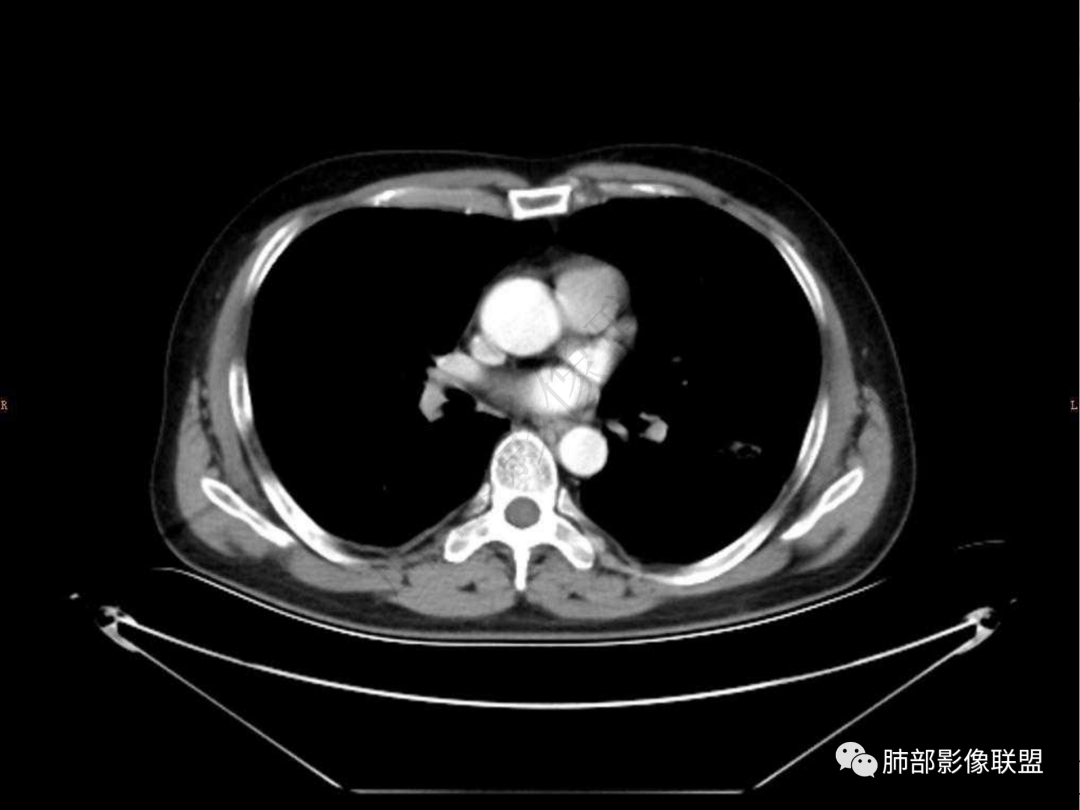

1.中年男性,咳嗽咳痰20余天,间断咯血2周

2.左肺下叶团片影,跨背段及内前基底段,实性部分类椭圆形,密度不甚均匀,可见毛刺及棘状突起,未见典型分叶及胸膜凹陷。病灶上下缘可见相应肺段支气管旁进侧出,管壁轻度增厚,未见狭窄阻塞。

3.周边较大范围磨玻璃影,边界相当模糊,小叶增厚明显。注意叶裂另一侧、左肺舌段亦可见磨玻璃影及增厚的小叶间隔。未见明确卫星病灶。

4.实性部分不均匀环形强化并显示一小范围低密度坏死区或空洞。较之肺窗,整体纵隔窗范围较小,提示病灶并不十分密实。抑或为不同时段图像。

5.双肺门及纵隔未见增大淋巴结。未见胸腔积液。